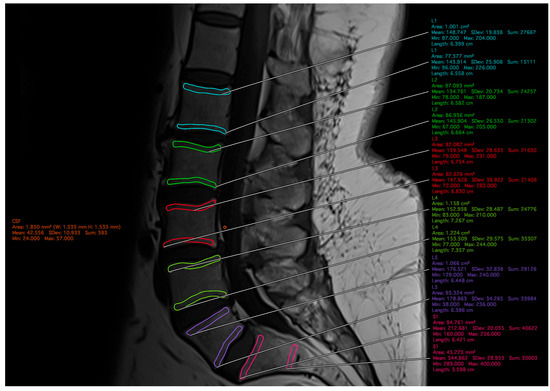

Endplate Bone Quality Assessment for Preoperative Planning and Patient-Specific Implementation in Lumbar Spine Surgery

by Wesley P. Jameson, Bailey D. Lupo, Andrew M. Schwartz, Andrew Daigle, Ahmed Anwar, Smith Surendran, Huy Tran, Christian Quinones, Deepak Kumbhare, Bharat Guthikonda and Stanley Hoang

J. Clin. Med. 2026, 15(7), 2800; https://doi.org/10.3390/jcm15072800 - 7 Apr 2026

Background/Objectives: Poor bone quality is strongly associated with adverse surgical events. Although dual-energy X-ray absorptiometry (DXA) remains the gold standard for bone mineral density (BMD) assessment, logistical barriers may limit its preoperative application. The Endplate Bone Quality (EBQ) score is an MRI-derived [...] Read more.

Background/Objectives: Poor bone quality is strongly associated with adverse surgical events. Although dual-energy X-ray absorptiometry (DXA) remains the gold standard for bone mineral density (BMD) assessment, logistical barriers may limit its preoperative application. The Endplate Bone Quality (EBQ) score is an MRI-derived metric quantifying subchondral bone quality at the vertebral endplate with demonstrated predictive value for cage subsidence following lumbar interbody fusion. However, EBQ has been measured exclusively at the operative level in surgical cohorts. This study aimed to assess level-specific EBQ scores across the entire lumbar spine and compare distributions across age, sex and osteoporosis subgroups. Methods: A single-institution retrospective review of T1-weighted lumbar MRI studies from patients evaluated for lower back pain from 2020 to 2025 was performed. EBQ was independently scored by two blinded raters at each disc space from L1–L2 to L5–S1 using 3 mm endplate ROIs normalized to a CSF ROI at L3. Interrater reliability was assessed via ICC, Pearson correlation, and RMSE. Patients were stratified by age (≤60 vs. >60 years), sex, and osteoporosis status, and subgroup comparisons were performed for overall and level-specific EBQ score. Results: A total of 96 patients with an average age of 61.0 ± 9.42 years were included in this study. The majority of patients included were female (87.5%), and 18.8% had been diagnosed with osteoporosis. EBQ scores demonstrated a progressive caudal increase across all subgroups from L2–L3 to L5–S1. Overall interrater reliability was acceptable (ICC = 0.76), with level-specific ICCs ranging from 0.70 to 0.83. No significant differences were observed between age or sex subgroups. Osteoporotic patients demonstrated significantly higher EBQ at L1–L2, L2–L3, and overall (all p < 0.05), with no significant differences at L3–L4 through L5–S1. Conclusions: This study provides normative, level-specific EBQ reference data throughout all levels of the lumbar spine. The increase in EBQ scores seen among caudal levels and reduced osteoporotic discriminatory power support the importance of level-specific context when interpreting EBQ thresholds. These findings may support future studies evaluating threshold development for EBQ. Full article